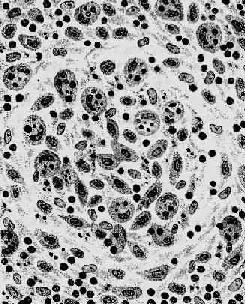

第三节 伤寒伤寒(typhoid fever)是由伤寒杆菌引起的一种急性传染病。病变主要特点是全身单核吞噬细胞系统的巨噬细胞反应性增生,尤以回肠淋巴组织的改变最为明显。临床上主要表现为持续性高热、神智淡漠、相对缓脉、脾肿大、皮肤玫瑰疹及血中白细胞减少等。 【病因及传染途径】 伤寒杆菌属沙门氏菌属,革兰染色阴性,呈短粗杆状,体周满布鞭毛,运动活泼,在含有胆汁的培养基中生长较好,因胆汁中的类脂及色氨酸可作为伤寒杆菌的营养成分。伤寒杆菌的菌体(O)抗原、鞭毛(H)抗原和表面(Vi)抗原能使人体产生相应的抗体。由于O及H抗原的抗原性较强,故可用于血清凝集试验(肥达反应,Widal reaction),以测定血清中的O及H抗体的效价来辅助临床诊断。菌体裂解时可释放强烈的内毒素,是伤寒杆菌致病的主要因素。目前利用沙门菌的invA基因和鞭毛素基因用PCR方法扩增进行分子杂交,可以检出3~300个活菌细胞,达到敏感和特异的效果。 伤寒患者和带菌者是本病的传染源。病菌随粪便和尿排出体外,通过污染饮水和食物,经口感染。苍蝇在本病的传播上起媒介作用。 【发病机制】 伤寒杆菌随污染的饮水或食物进入消化道后,穿过小肠粘膜上皮细胞侵入肠壁的淋巴组织,特别是回肠下段的集合淋巴小结和孤立淋巴小结,并沿淋巴管至肠系膜淋巴结。在这些淋巴组织内,伤寒杆菌一方面被巨噬细胞吞噬,并在其中生长繁殖;另一方面经胸导管进入血液,引起菌血症。血液中的病菌很快被全身单核吞噬细胞系统如肝、脾,骨髓和淋巴结中的巨噬细胞吞噬,并进一步在其中大量繁殖。在这一段时间内,虽然有单核吞噬细胞系统的增生反应,但临床上无明显症状,称为潜伏期,一般10天左右。 此后,在全身单核吞噬细胞系统内繁殖的病菌及其释放的内毒素再次大量进入血液,并随之散布至全身各脏器和皮肤等处,引起败血症和毒血症,呈现全身中毒性症状和病理改变。病变主要发生于回肠末段,其肠壁的淋巴组织出现明显的增生肿胀,此时相当于疾病的第一周,血培养常为阳性。随着病程的发展,在发病后的第2~3周,伤寒杆菌在胆囊内繁殖到一定数量,大量病菌随胆汁再度进入小肠,又可穿过肠粘膜再次侵入肠道淋巴组织,使原已致敏的肠壁淋巴组织发生强烈的过敏反应,导致坏死、脱落和溃疡形成。伤寒杆菌随同脱落的坏死组织和粪便排出体外,故此段时间粪便培养易获阳性结果。与此同时,人体的免疫力逐渐增加,血中的抗体不断上升,肥达反应在病程第二周以后多数出现阳性。但近年来有研究证明血中抗体滴度的高低与患者对伤寨杆菌的抵抗力无关,而系细胞免疫在对抗病菌上起主要作用。即在致敏T细胞所产生的某些淋巴因子的作用下,增强巨噬细胞的吞噬、灭菌功能。在病程的第四周,随着免疫力的增强,血液和器官内的细菌逐渐消失,中毒症状减轻、消失,病变随之愈合而告痊愈。 【病变及临床病理联系】 伤寒是主要累及全身单核吞噬细胞系统的感染性疾病,病变突出表现在肠道淋巴组织,肠系膜淋巴结、肝、脾和骨髓等处。此外,由于败血症的存在,在病菌及其释放的内毒素作用下,全身许多器官也可受累。 伤寒杆菌引起的炎症属急性增生性炎症,主要是巨噬细胞的增生。其吞噬能力十分活跃,胞浆中常吞噬有伤寒杆菌、受损的淋巴细胞、红细胞及坏死细胞碎屑,在病理诊断上具有一定的意义,故常称这种细胞为伤寒细胞。伤寒细胞常聚集成团,形成小结节,称为伤寒肉芽肿或伤寒小结(图18-19)。革兰染色可见伤寒细胞胞浆内含有被吞噬的伤寒杆菌。伤寒杆菌引起的炎性反应的特点是病灶内无中性粒细胞渗出。

图18-19 伤寒肉芽肿模式图 图示伤寒小结内大量增生的伤寒细胞,胞浆内含有红细胞及组织碎屑等 1.肠道病变 以回肠下段的集合和孤立淋巴小结的病变最为常见和明显。按病变自然发展过程可分为以下四期,每期约1周。 (1)髓样肿胀期:在起病的第一周,回肠下段淋巴组织明显肿胀,凸出于粘膜表面,色灰红,质软。其中以集合淋巴小结肿胀最为突出,表面形似脑回样隆起(图18-20)。肠粘膜有充血、水肿、粘液分泌增多等变化。